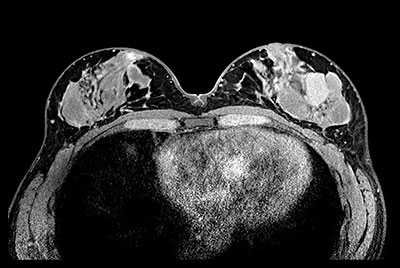

Breast biopsy with dS Sentinelle Breast coil

Dynamic Breast imaging with SmartSpeed AI

Breast 3D and 4D imaging

Breast Ca with T1 perfusion

Breast with Compressed SENSE on BlueSeal magnet

Breast imaging with Compressed SENSE

Breast lesion

Breast imaging using SmartExam

SmartBreast - ds Breast 7ch coil

SmartBreast - ds Breast 16ch coil

dS Breast Adaptive 16ch coil